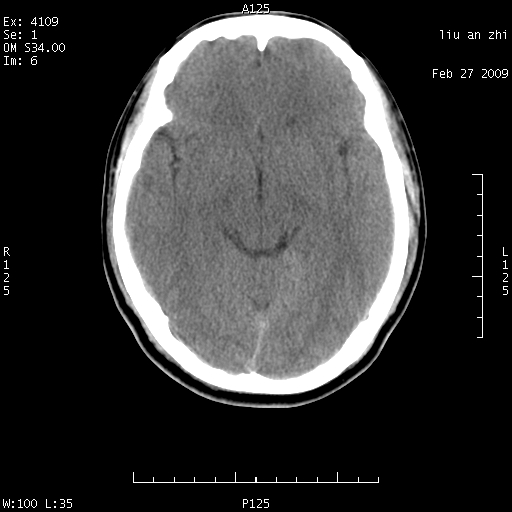

患者:男,32岁 被打伤后3天,自感头昏头痛作头颅ct检查。请大家看一下想什么??

7天后复查头颅ct片:

请注意小脑幕!!!

ct18448的结果:mri检查左侧天幕下血肿

以下是引用深蓝一号在2009-3-9 16:22:00的发言:[br]ct18448的结果:mri检查左侧天幕下血肿。